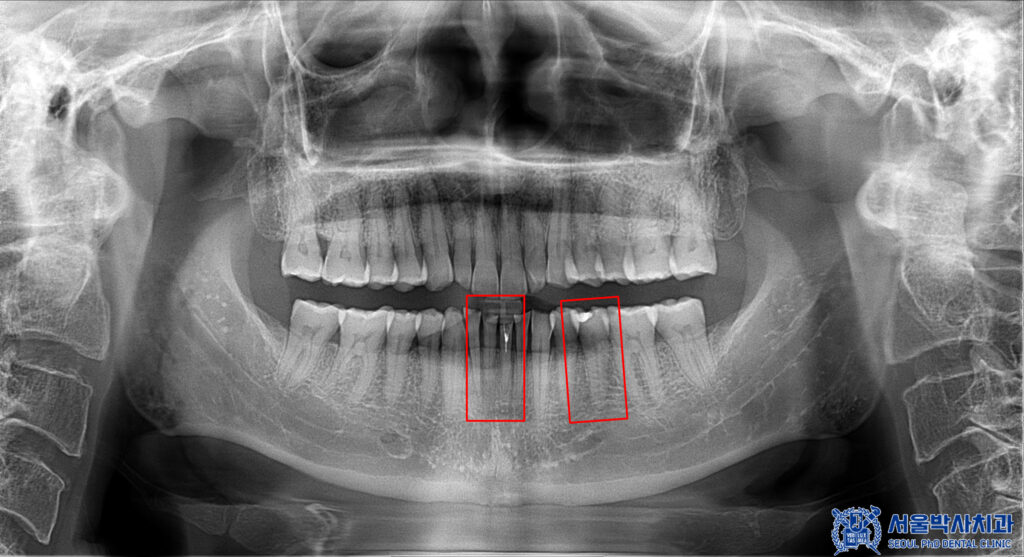

또한 파노라마를 확인해 보니,

왼쪽 아래 앞니는 과거에

신경치료가 시행된 치아였으나

치아 뿌리 끝 부위에 염증 소견이

관찰되었습니다.

이에 따라 기존 치료 부위를

다시 정리하고 염증을 제거하기 위해

재신경치료를 진행하기로

결정하였습니다.

더불어 해당 치아와 맞닿아 있는

옆 앞니 역시 뿌리 끝 염증이 확인되어,

염증의 확산과 추가적인 문제를 예방하기 위해

함께 신경치료를 시행하기로 하였습니다.

아울러 작은 어금니의 경우,

기존 충전재 아래로 충치가 확인되어

충전재와 우식 부위를 제거한 후

치아를 보호하고 기능을 회복하기 위해

크라운 치료를 진행하는 것으로

치료 계획을 수립하였습니다.